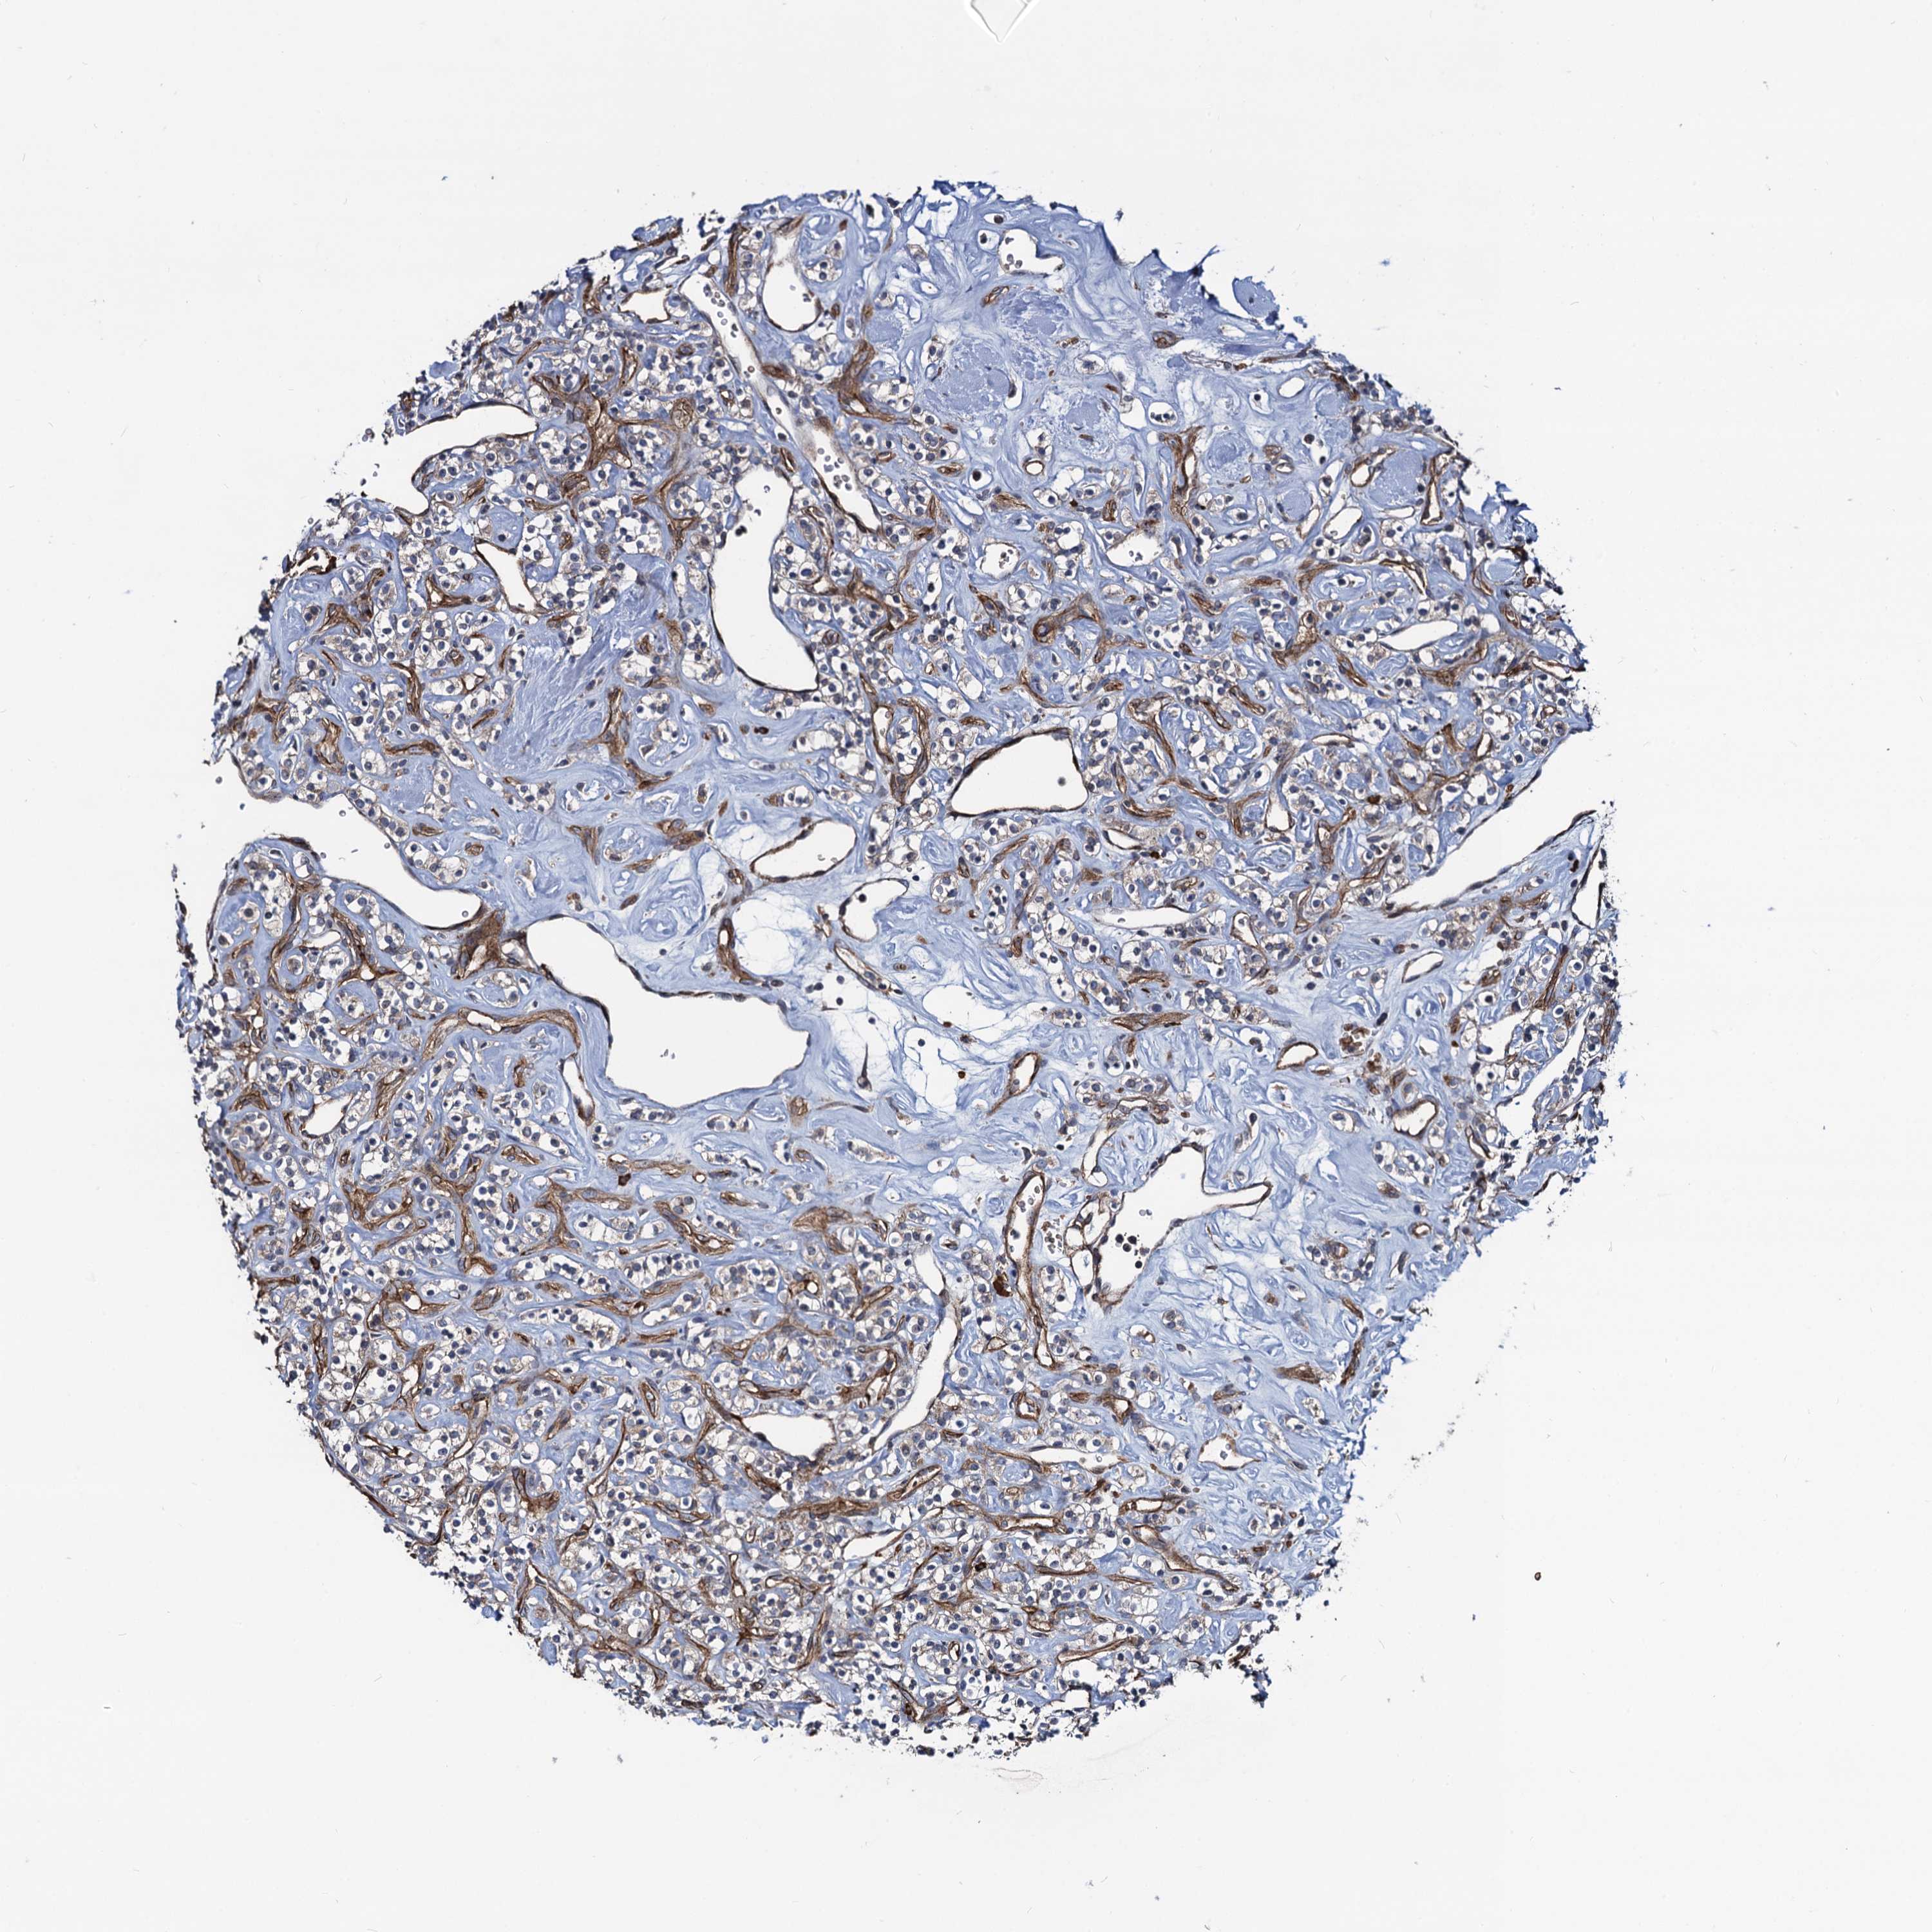

KIDNEY RENAL CLEAR CELL CARCINOMA (TCGA) - Interactive survival scatter ploti

The Survival Scatter plot shows the clinical status (i.e. dead or alive) for all individuals in the patient cohort, based on the same data that underlies the corresponding Kaplan-Meier plots. Patients that are alive at last time for follow-up are shown in blue and patients who have died during the study are shown in red.

The x-axis shows the expression levels (FPKM) of the investigated gene in the tumor tissue at the time of diagnosis. The y-axis shows the follow-up time after diagnosis (years). Both axes are complimented with kernel density curves demonstrating the data density over the axes. The top density plot shows the expression levels (FPKM) distribution among dead (red) and alive patients (blue). The right density plot shows the data density of the survived years of dead patients with high and low expression levels respectively, stratified using the cutoff indicated by the vertical dashed line through the Survival Scatter plot. This cutoff is automatically defined based on the FPKM cutoff that minimizes the p-score. The cutoff can be changed by dragging the vertical line or by entering a cutoff value in the square labeled "Current cut-off".

Under the Survival Scatter plot the p-score landscape (black curve; left axis) is shown together with dead median separation (red curve; right axis). Dead median separation is the difference in median mRNA expression between patients who have died with high and low expression, respectively. It is calculated as follows: median FPKM expression of dead patients with high expression - median FPKM expression of dead patients with low expression. This is intended to aid the user in visually exploring custom cutoffs and the associated p-scores and dead median separation.

Individual patient data is displayed and can be filtered by clicking on one or more of the category buttons on the top of the page. Categories describing expression level and patient information include: high, low, alive, dead, female, male and tumor stages. The scale of the x-axis can be toggled between linear and log-scale by clicking on the "x log" button. Mouse-over function shows TCGA ID, patient information and mRNA expression (FPKM) for each patient.

& Survival analysisi

Kaplan-Meier plots summarize results from analysis of correlation between mRNA expression level and patient survival. Patients were divided based on level of expression into one of the two groups "low" (under cut off) or "high" (over cut off). X-axis shows time for survival (years) and y-axis shows the probability of survival, where 1.0 corresponds to 100 percent.

KXD1 is not prognostic in Kidney Renal Clear Cell Carcinoma (TCGA)

Best expression cut offi

Based on the FPKM value of each gene, patients were classified into two groups and association between prognosis (survival) and gene expression (FPKM) was examined. The best expression cut-off refers the FPKM value that yields maximal difference with regard to survival between the two groups at the lowest log-rank P-value. Best expression cut-off was selected based on survival analysis .

When clicking on this number, the vertical dashed line indicating cut-off, the interactive survival plot, and the Kaplan-Meier curve will be adjusted to show results based on the best expression cut-off.

: 101.77

Median expressioni

Median expression refers to the median FPKM value calculated based on the gene expression (FPKM) data from all patients in this dataset. When clicking on this number, the vertical dashed line indicating cut-off, the interactive survival plot, and the Kaplan-Meier curve will be adjusted to show results based on the median expression.

: N/A

Median follow up timei

Median follow up time refers to the median time (years) after diagnosis with this type of cancer, based on clinical data from all patients in this dataset.

P scorei

Log-rank P value for Kaplan-Meier plot showing results from analysis of correlation between mRNA expression level and patient survival.

N/A

5-year survival highi

5-year survival for patients with higher expression than the expression cutoff.

For melanoma and glioma, 3-year survival is shown.

5-year survival lowi

5-year survival for patients with lower expression than the expression cutoff.

TCGA RNA samplesi

RNA-seq data is reported as average FPKM (number Fragments Per Kilobase of exon per Million reads), generated by the The Cancer Genome Atlas (TCGA) .

Normal distribution across the dataset is visualized with box plots, shown as median and 25th and 75th percentiles. Points are displayed as outliers if they are above or below 1.5 times the interquartile range. FPKM values of the individual samples are presented next to the box plot.

Average pTPM 86.6

Number of samples 521